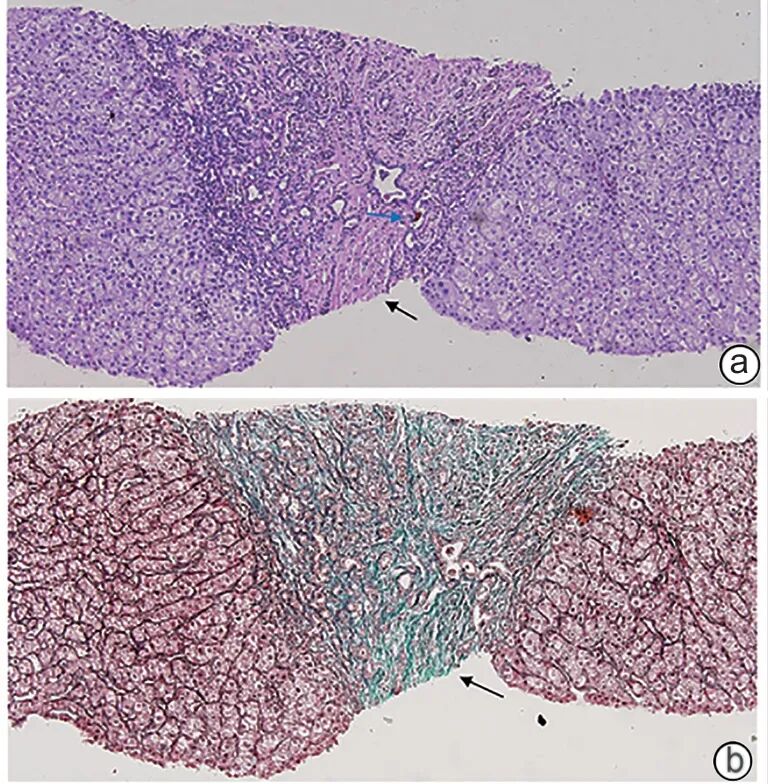

注: 男性,23岁。a(HE染色,×40)、b(HE染色,×100):肝实质为宽阔的纤维间隔不规则分隔(黑色箭头示纤维间隔),间隔为纤维性,其内可见增生的、多数形状不规则的小胆管,少数呈分支状,有的轻度扩张含浓缩胆汁,间隔内可见小动脉,未见相应口径的门静脉;间隔与肝实质界清,部分交界带见细胆管反应性增生。c(CK7免疫组化染色,×100):显示交界带内增生的细胆管。d(网织+Masson染色,×100):显示宽阔的纤维间隔(黑色箭头示纤维间隔)。

图1 CHF的病理学改变

注: 男性,24岁,伴Caroli病。a(HE染色,×100):肝实质为多条宽阔纤维带所分隔(黑色箭头示纤维间隔区域),纤维带内有的可见多数大小不一的幼稚小胆管,少数管腔内含胆汁(蓝色箭头示胆管内淤积的胆汁);有的含扩张的胆管,衬附单层立方上皮或矮柱状上皮,周围未见明显炎症。肝实质内肝板排列尚整,部分肝细胞内含脂褐素,偶见小坏死灶。b(网织+Masson染色,×100):显示宽阔的纤维间隔区域(黑色箭头示纤维间隔区域)。

图2 CHF合并Caroli病的病理学改变